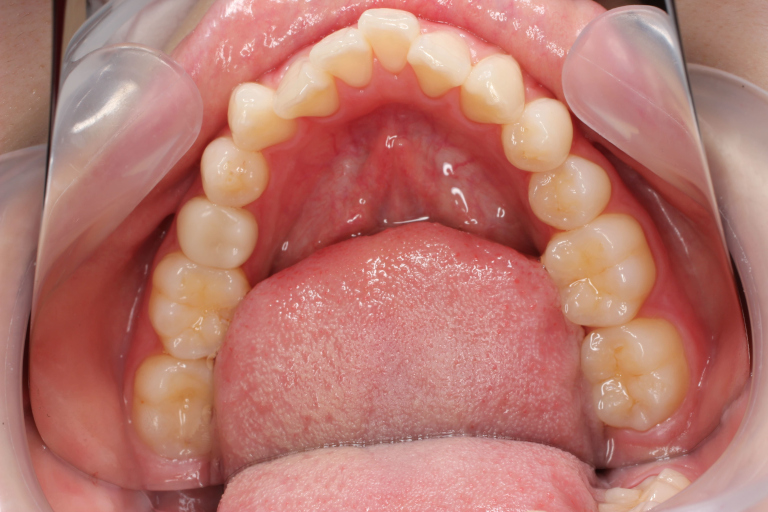

Before

After

| 主訴 | 歯並びの乱れ(叢生)があり、口元の突出感を抑えたい |

| 治療内容 | インビザラインを用いた治療 (非抜歯ケース) |

| 治療期間 | 1年7ヶ月 |

| 治療費用 | 基本料金:660,000円 調整料:3,300円 × 24回 |

| リスク | 取り外し式装置で、1日24時間中22時間使用しなければならず、しっかりと装置を装着できないと歯は思ったように動きません。 |